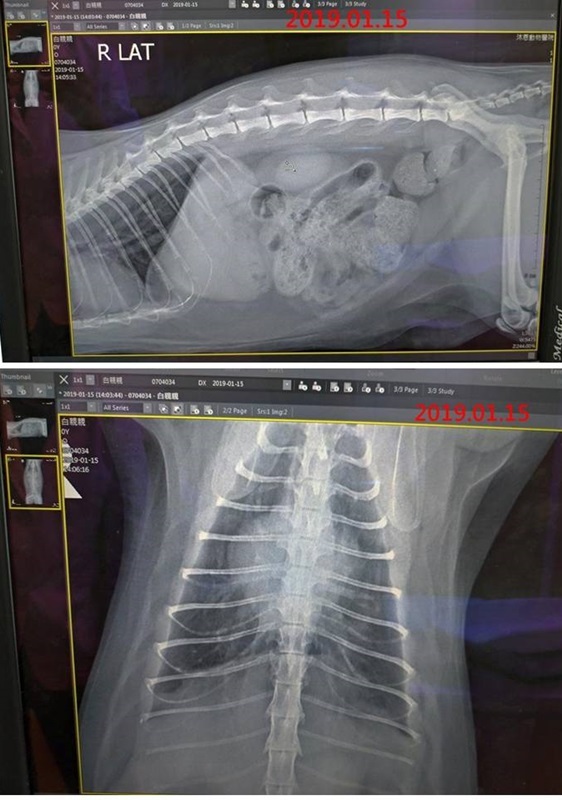

醫師觸診白親親的腸道覺得大便不是很硬,可以用手掐斷,應該可以自行排出。X光片顯示白親親腸道裡面大便不少,但是並沒有異物纏繞的樣子。

不過X光片同時也看到白親親的心臟有一邊(右心房)比較大,形狀偏右,但因為並沒有咳嗽、氣喘等生理症狀,暫時不須理會,如果希望有更進一步的診斷就需要照超音波。

在服藥、氣霧治療三週後,白親親的鼻涕淚眼已有改善,但照護員看到白親親便便時似乎很吃力,解出的便便很硬且表面有帶血,於是再度至沐恩醫院檢查,X光顯示腸道無異物、便便很多,但觸診便便並無偏硬,可再觀察,只是同時發現她的心臟右心房比較大,形狀偏右,但之後需要觀察有沒有頻繁咳嗽、氣喘等症狀。